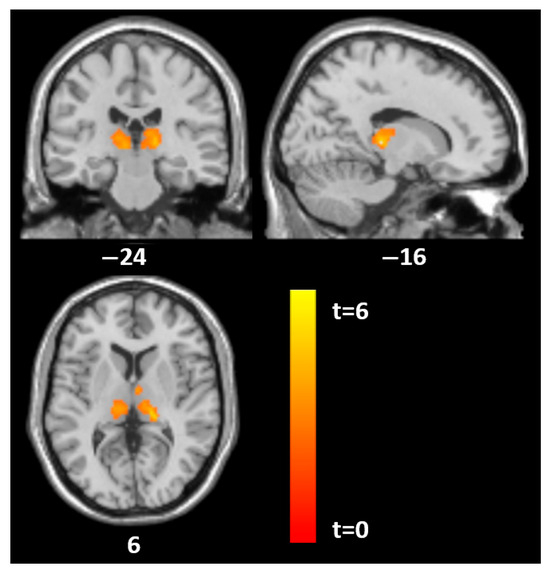

| Histrionic | |||||||

| Thalamus | 845 | −17 | −26 | 5 | 6.5 | 0.002 | 0.01 |

| 666 | 15 | −20 | 9 | 4.7 | 0.009 | ||

| Left superior parieto-occipital | 905 | −30 | −66 | 54 | 5.9 | 0.001 | |

| Borderline | |||||||

| Thalamus | 1149 | 0 | −21 | 9 | 4.8 | <0.001 | 0.01 |

| −5 | −11 | 12 | 4.3 | ||||

| Antisocial | |||||||

| Thalamus | 1227 | −9 | −21 | 5 | 5.1 | <0.001 | 0.01 |

| 14 | −20 | 6 | 4.4 | ||||